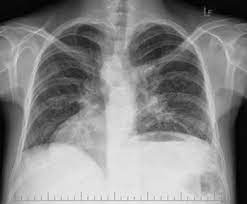

Rozsah symptómov primárnej ciliárnej dyskinézy sa u postihnutých osôb líši. Príznaky často začínajú krátko po narodení a môžu zahŕňať kašeľ, zvracanie, dusenie a atelektázu pľúc (neonatálna respiračná tieseň). Postihnutí jedinci majú často chronické infekcie dutín, stredného ucha a pľúc, ako aj chronický kašeľ, nadbytok hlienu a stratu sluchu. Opakujúce sa respiračné infekcie môžu viesť k ireverzibilnému zjazveniu a dilatácii priedušiek (bronchiektázii) a vážnemu poškodeniu pľúc.

Pohyb riasiniek môže byť tiež dôležitý pri umiestnení orgánu do vyvíjajúceho sa embrya. Približne 50% osôb s PCD má Kartagenerov syndróm, pri ktorom sú vnútorné orgány vrátane srdca, pečene, sleziny a čreva na opačnej strane tela (situs inversus totalis). Niektorí jedinci s PCD majú stav nazývaný heterotaxia (situs ambiguus), pri ktorom sú vnútorné orgány abnormálne umiestnené a majú abnormálnu štruktúru. Približne 12% pacientov s PCD má heterotaxiu a podskupina týchto pacientov má vrodené srdcové chyby, ktoré môžu byť závažné a život ohrozujúce.